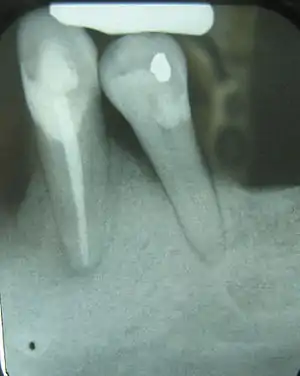

Crown-to-root-ratio is the ratio of the length of the part of a tooth that appears above the alveolar bone versus what lies below it.[1] It is an important consideration in the diagnosis, treatment planning and restoration of teeth, one that hopefully guides the plan of treatment to the proper end result.

These terms can also be used to refer to the clinical sense of the words, as relative crown and relative root, by describing how much tooth remains surrounded by bone. As the inflammation associated with periodontal disease causes the bone to resorb and disappear, revealing more of the root structure, the effective crown height in relation to the effective root height is reduced and the prognosis shifts from favorable to unfavorable.

Clinically, the anatomical definitions don't really matter; what is important in terms of support for the teeth within the bone is how much of the teeth remain embedded; this is where the crown-to-root ratio becomes important.

The natural crown-to-root ratio is thus termed a favorable crown-to-root ratio, because the root system existing within the surrounding bone is more than sufficient to support the tooth under normal physiologic stresses. After some bone loss is incurred, though, and more root structure is visible outside of the supporting bone, not only is there less effective root support, but there is an increased height of revealed tooth structure that this now diminished submerged root is responsible for supporting. In a way, then, each millimeter of lost bone contributes, for example, to a millimeter of less support and a millimeter of more structure to support. As can be extrapolated, this can easily become a very serious problem once three, four or five millimeters of bone have been lost due to periodontal disease.[3] The minimum crown-to-root ratio necessary is 1:1; any less support provided by the roots drastically reduces the prognosis of the tooth and its restoration.